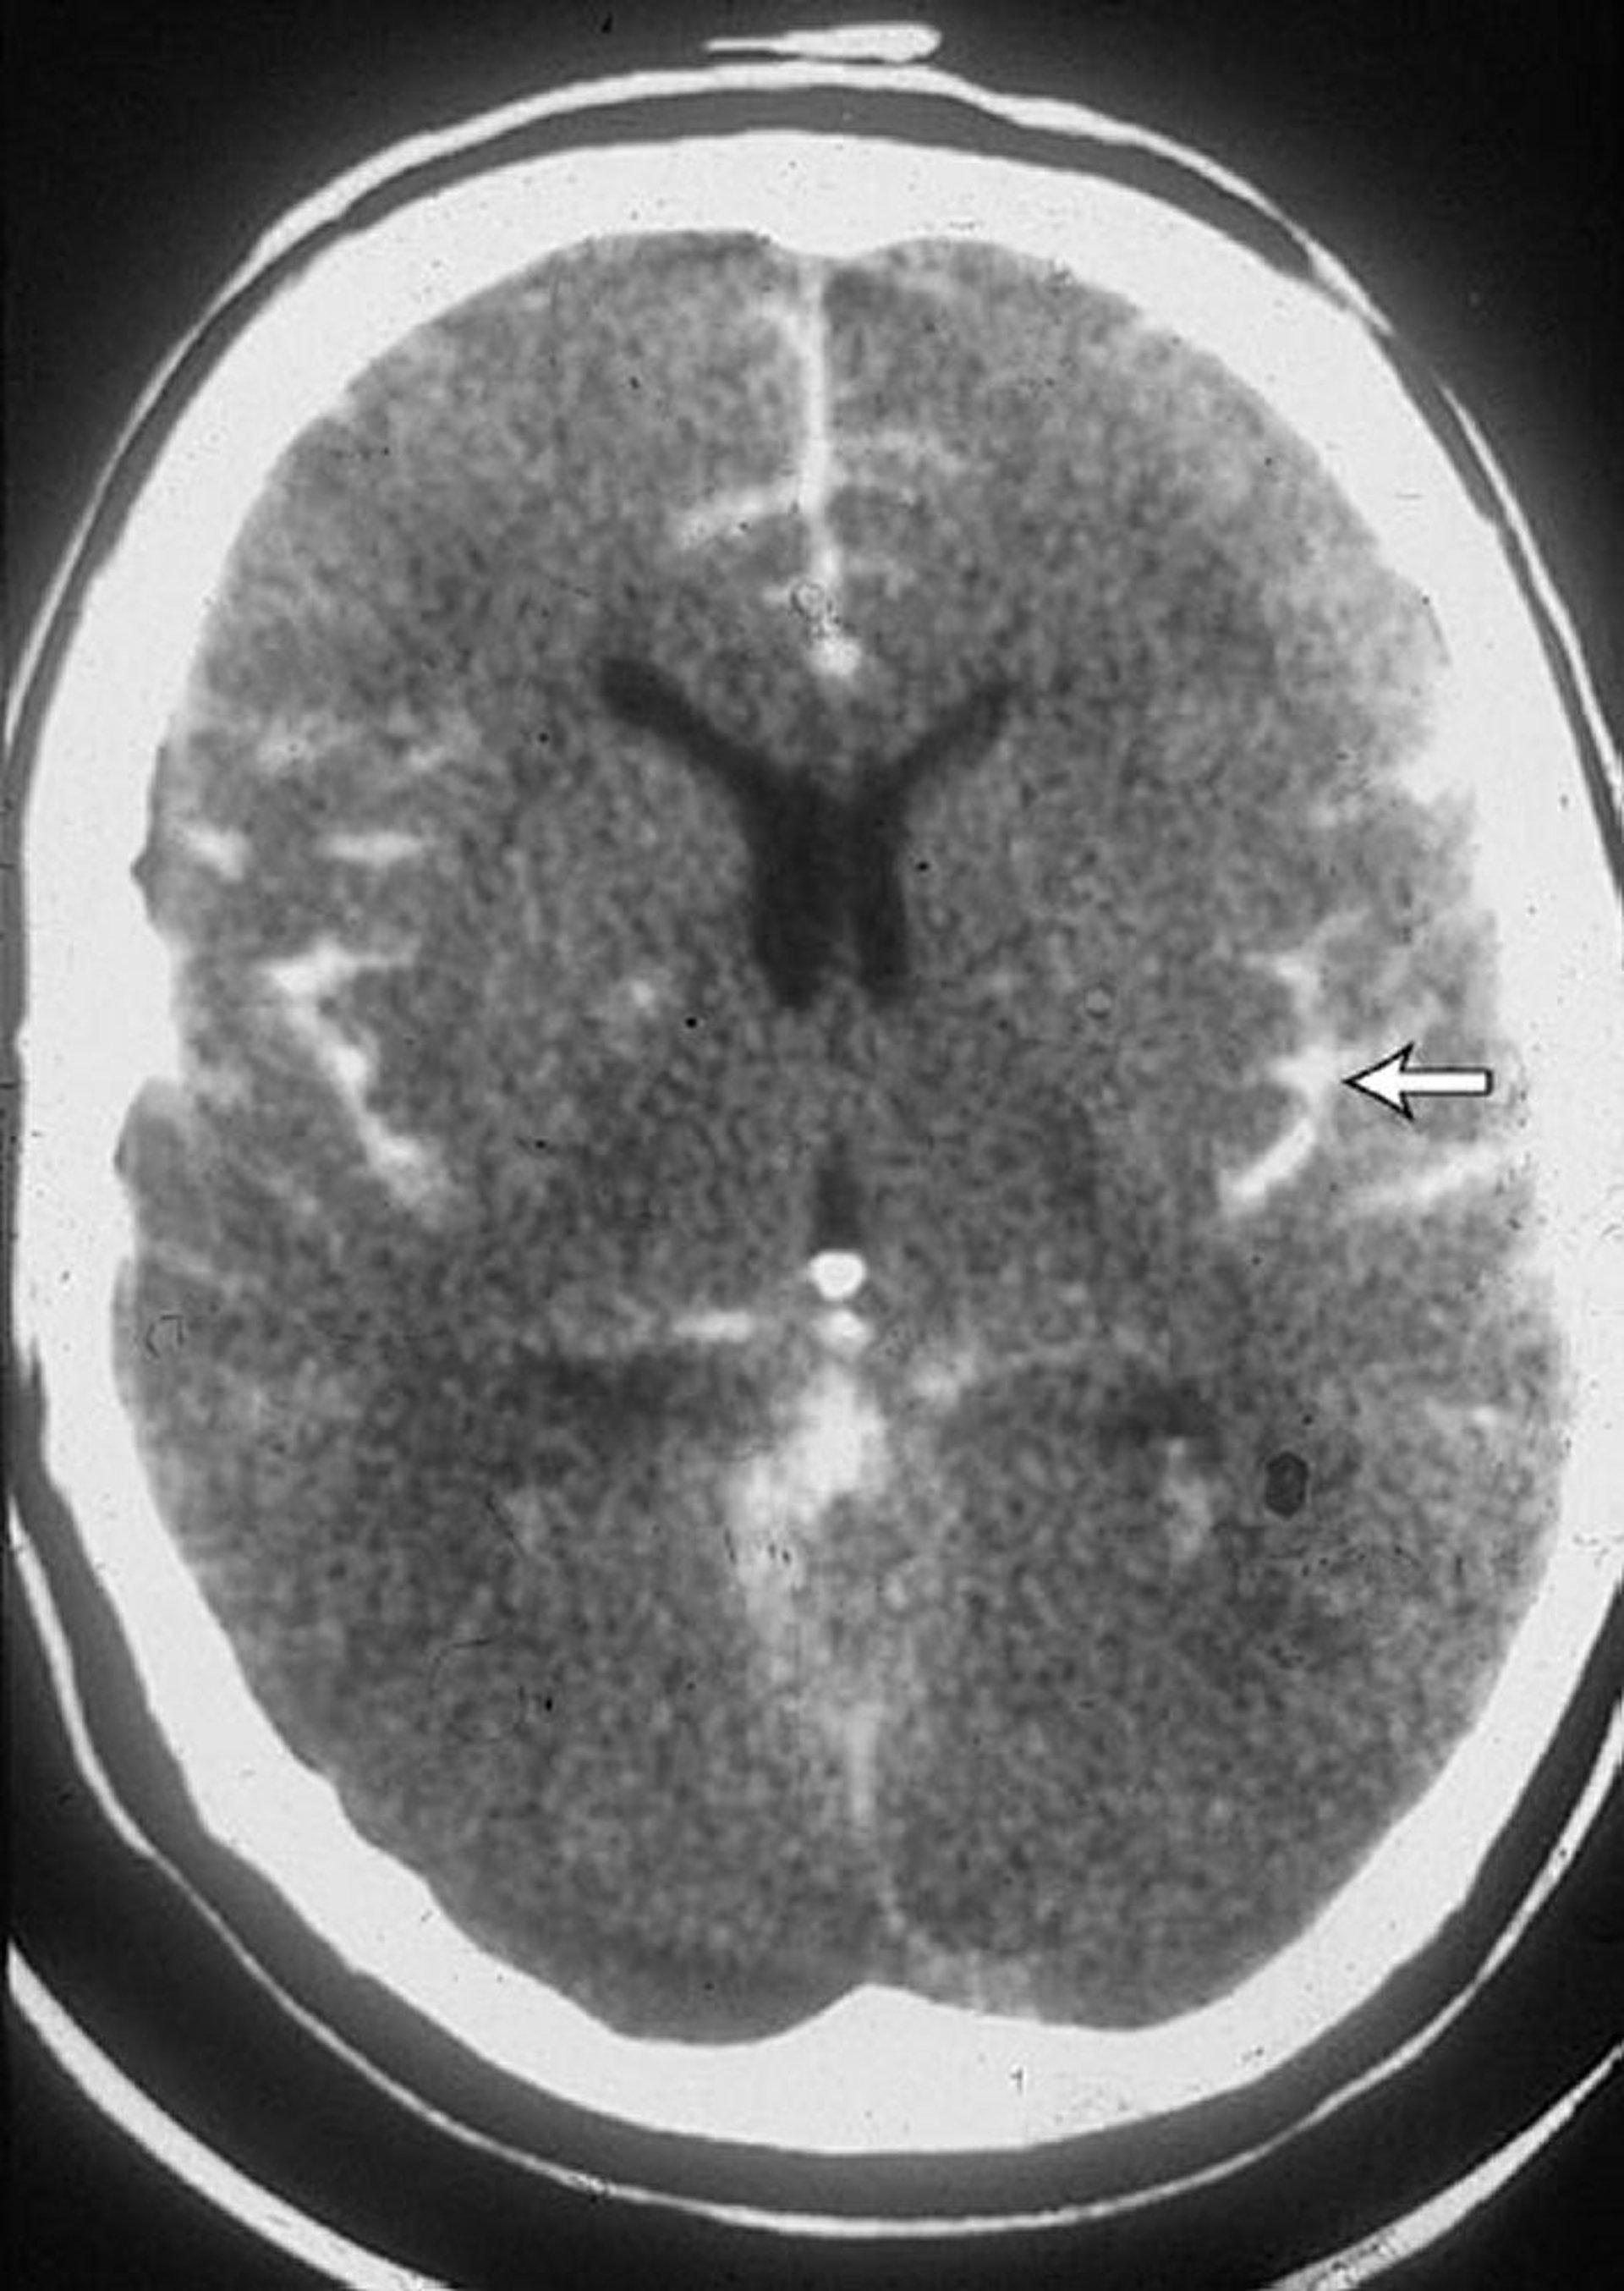

Noncontrast CT is performed within 6 hours of symptom onset. When performed within this time frame, this test has very high sensitivity. Therefore, if this test does not detect a subarachnoid hemorrhage, no other testing is needed as long as patients have a normal physical examination, no meningeal signs, and no anemia. MRI is comparably sensitive but less likely to be immediately available. False-negative results occur if the volume of blood is small or if there is profound anemia such that blood is isodense with brain tissue.

If bleeding is indicated by CT or lumbar puncture, angiography is performed to confirm the diagnosis and to identify the site of the aneurysm or arteriovenous malformation causing the bleeding. Cerebral angiography is more invasive than MRA or CTA but provides more information. However, CTA has largely replaced cerebral angiography for the diagnosis of aneurysms within the skull.